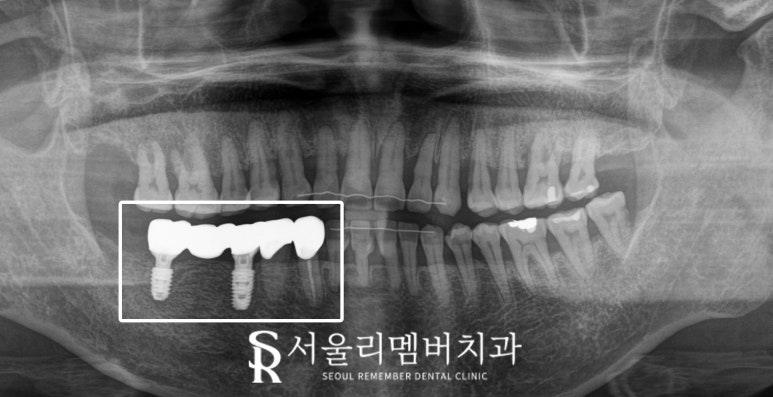

(2) 45=47번

: 브릿지 아래 이차우식 생긴 45번,

치근 부러진 47번

발치 후 임플란트 브릿지 새로 제작

2024.10.27

구체적으로 세워두었던 계획에 따라

단계별로 진행하여

구강 건강을 되찾은 모습입니다.